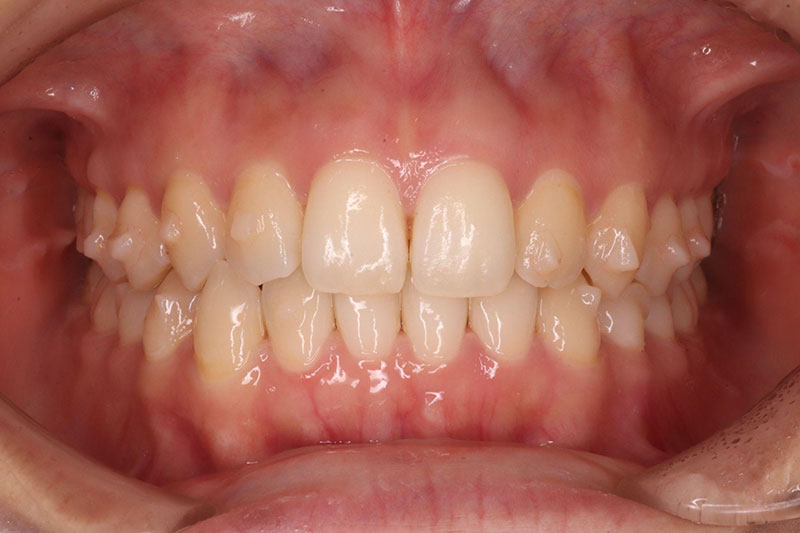

矯正治療で歯を移動すると、歯茎や歯槽骨が下がることがあります(歯肉退縮・歯槽骨吸収)。歯槽骨が薄い方、年齢が高い方は起こりやすい傾向にあります。

矯正治療後、下顎前歯部の歯茎が下がっています

また歯肉退縮と相まって、歯と歯の間に「ブラックトライアングル」というすき間ができることがあります。特に前歯にできると、見た目が気になるかもしれません。

これは、歯並びが良くなることで、今まで隠れていた歯ぐきのすき間が見えるようになったり、歯周組織が引き締まったりしてできるもので、特に異常ではありません。歯の形が三角形に近いと、ブラックトライアングルはできやすくなります。

歯を配列したあと、下顎前歯部にブラックトライアングルが生じた